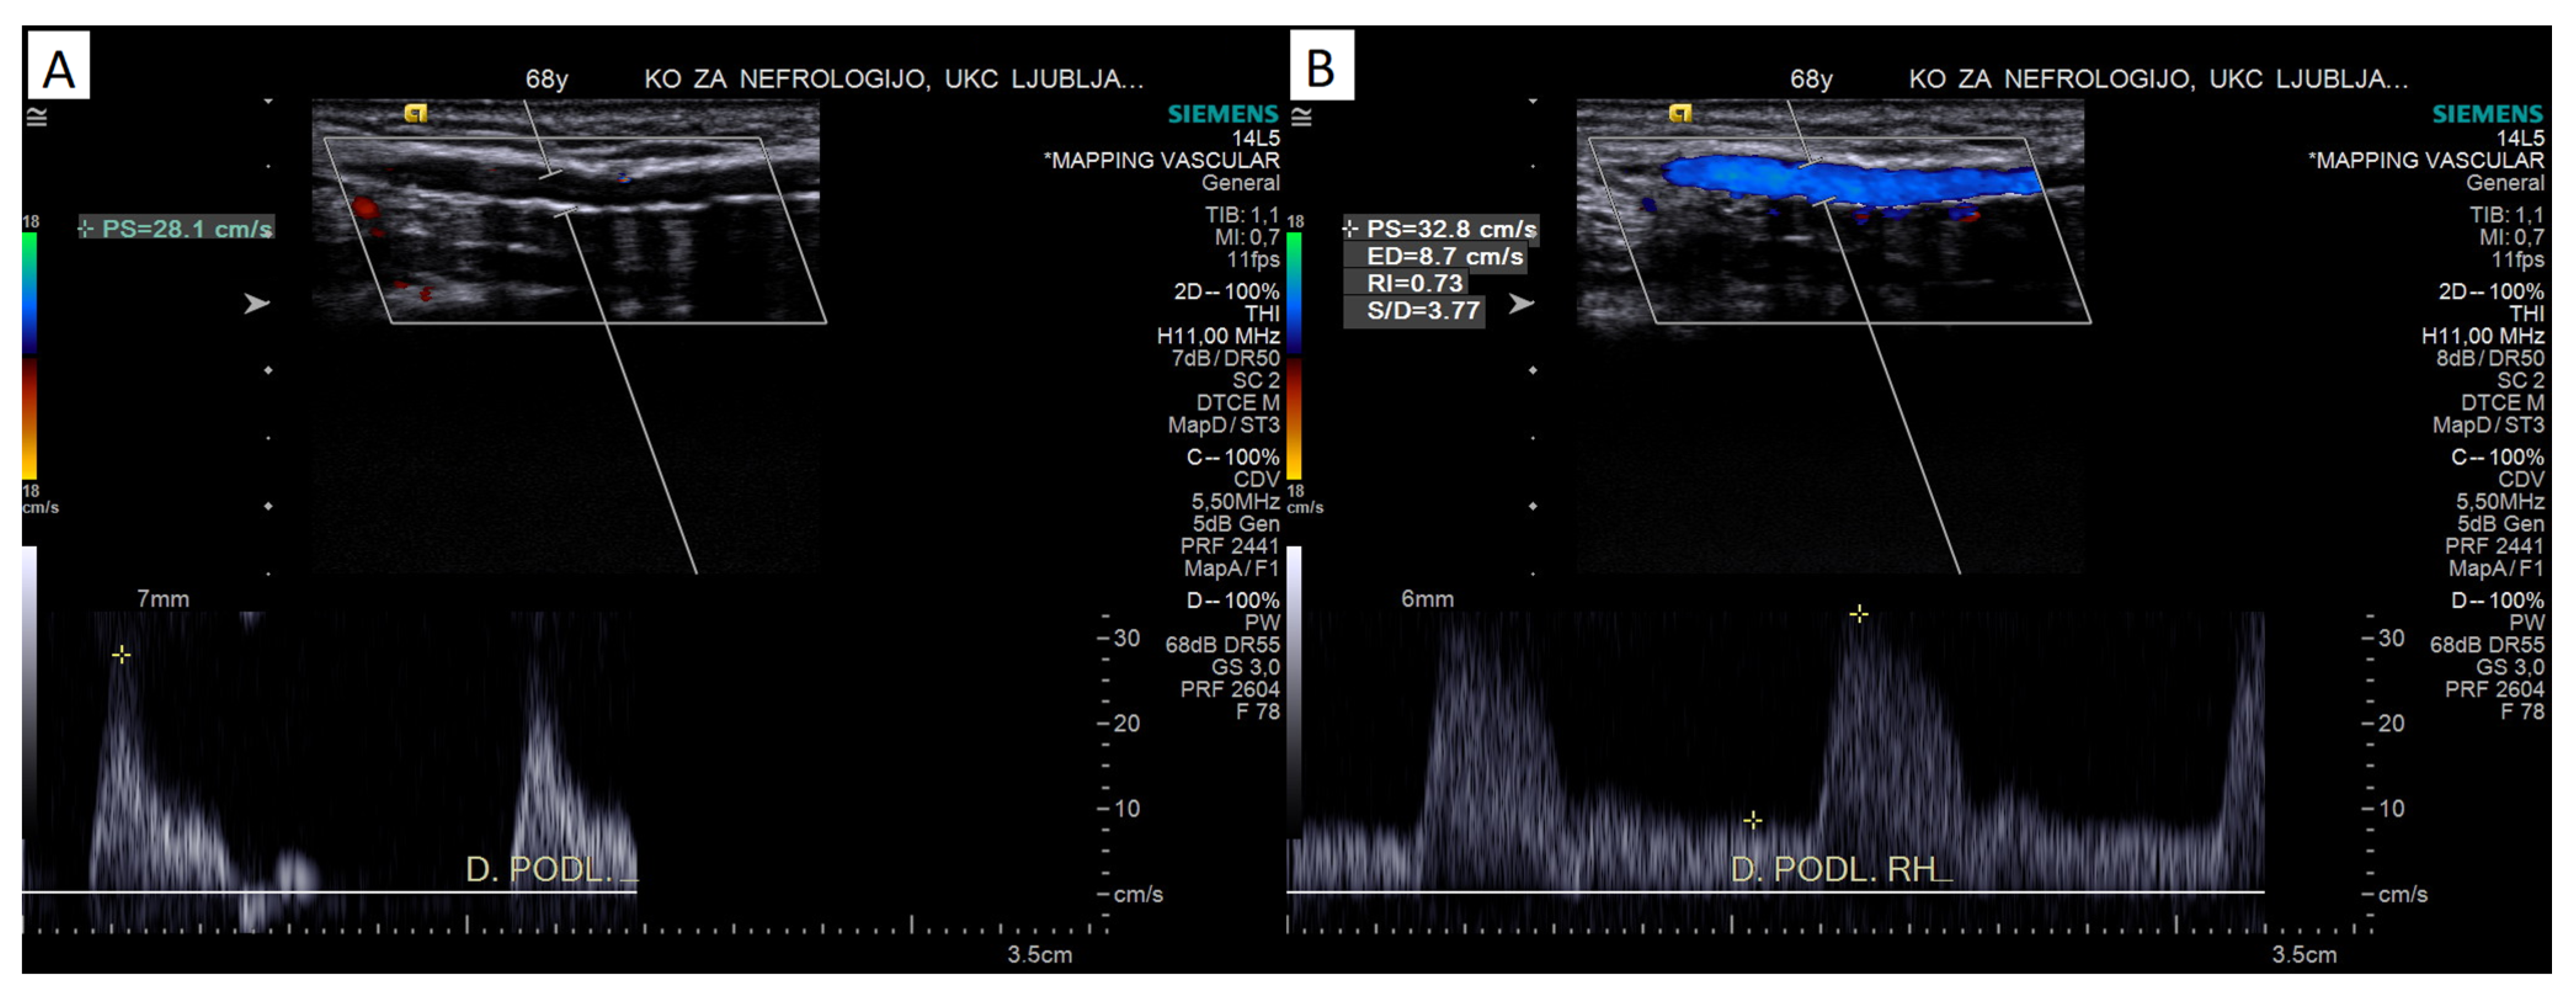

4.1.5. Color Doppler Assessment

4.2.2. Pulsed-Wave Doppler Assessment

Peak Systolic Velocity

Doppler Curve Assessment, Acceleration Parameters

Reactive Hyperemia Test